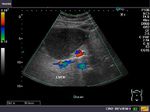

This middle aged male patient shows a cystic lesion of 1.9 cms. in the left lobe of liver on ultrasound imaging. However, what was interesting was the close proximity of the cystic lesion with a tributary of the portal vein. Color and Power Doppler images of the hepatic cyst showed no flow in the liver cyst. However, the spectral Doppler trace showed faint pulsations within this lesion. These pulsations appear to be transmitted from the abdominal aorta and appear insignificant. Thus we arrived at a diagnosis of a simple cyst of the left lobe of the liver, based on these ultrasound and Color Doppler images. Absence of flow in this cyst ruled out possibilities like a vascular lesion like aneurysm of the portal vein or AVM. The liver also shows moderate fatty change. This cyst was an incidental finding as the patient had no symptoms related to this lesion.